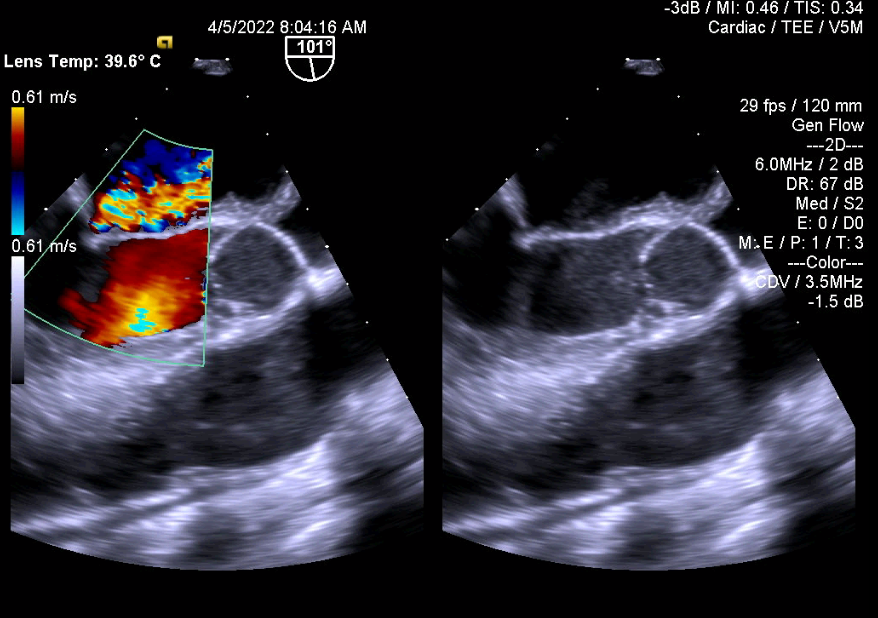

1.Huyết khối gây kẹt van hai lá cơ học:

2.Đánh giá hiệu quả điều trị bằng thuốc tiêu sợi huyết đối với kẹt van cơ học (cùng bệnh nhân ở trên)